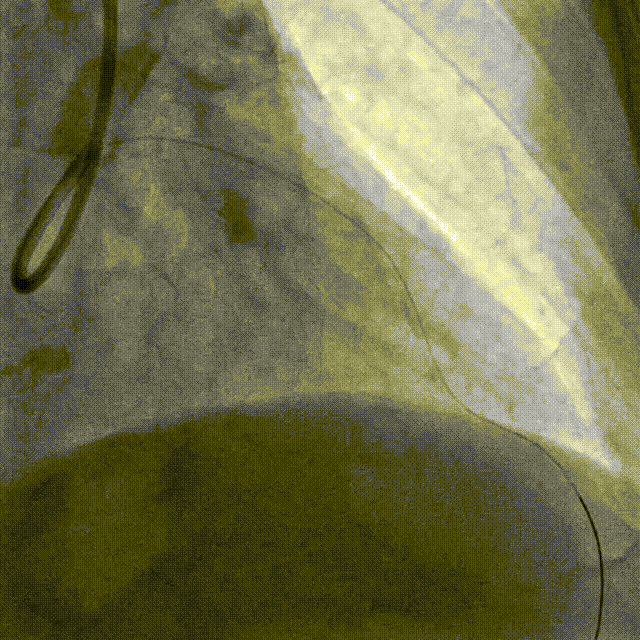

PCI-RCA TR, 7F JR4.0 ROTA with 2.0mm burr

Angiography post-ROTA